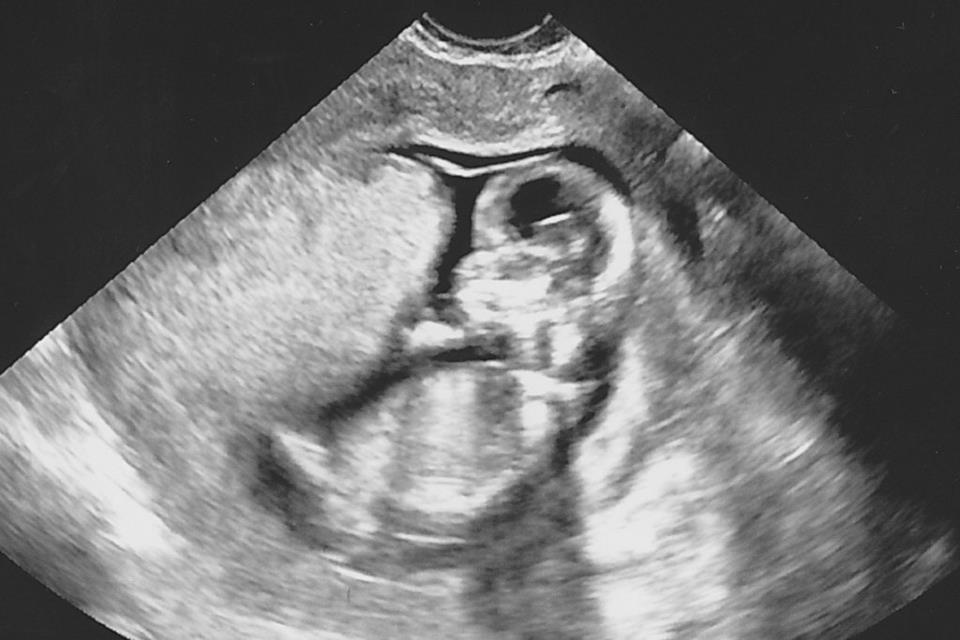

Please guess away!! Attachment 6863

boy

Boy (angle).

may be boy

Not at all clear sorry xx

I don't see any clues, so 50/50.

Sorry, can't make it out...GL!